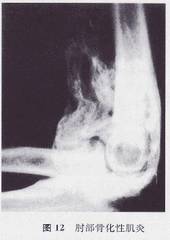

? 在锻炼过程中,要控制好活动量,避免暴力操作。一定要避免在练习时造成重复损伤,以免出现骨化性肌炎(上图)。一旦出现骨化性肌炎,将严重影响关节功能。锻炼前热敷,可以放松软组织,锻炼后冷敷可以减轻组织水肿。